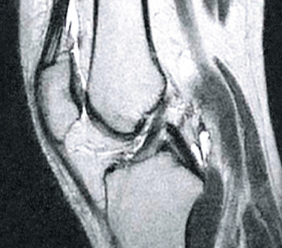

PRED

PO

Fotografia vľavo ukazuje prázdne miesta v kĺbovom puzdre, ktoré sú výsledkom nadmernej hydratácie tkaniva. Po ošetrení bola štruktúra synoviálnej tekutiny prestavaná (foto vpravo) a znovu získala svoju viskoelastickú konzistenciu a klzné vlastnosti. Kosti sú správne „namazané“, aby sa o seba neodierali, pretože sa obnovili tlmiace funkcie kĺbu.